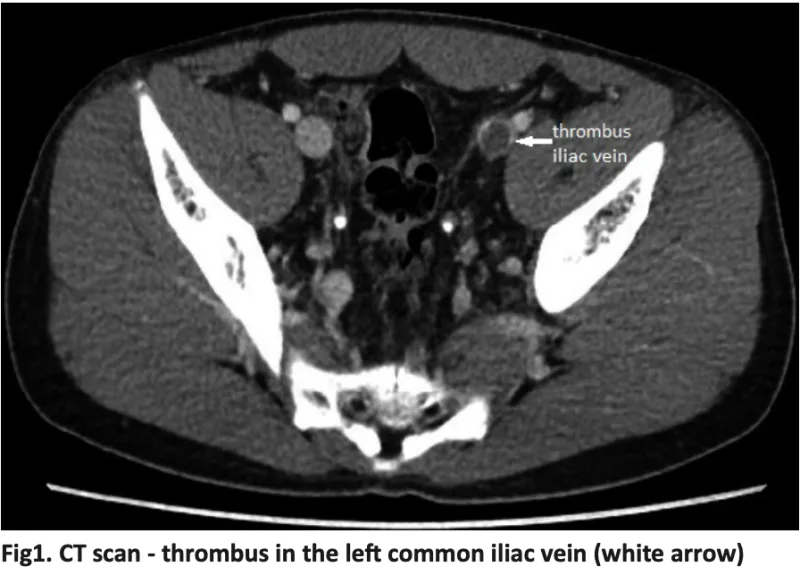

本来は, 造影剤によって白く描出される静脈の中に血栓が黒い陰影が認められます.

造影CTでは骨折側の総腸骨静脈から後脛骨静脈にかけて, 広範囲に血栓が存在.